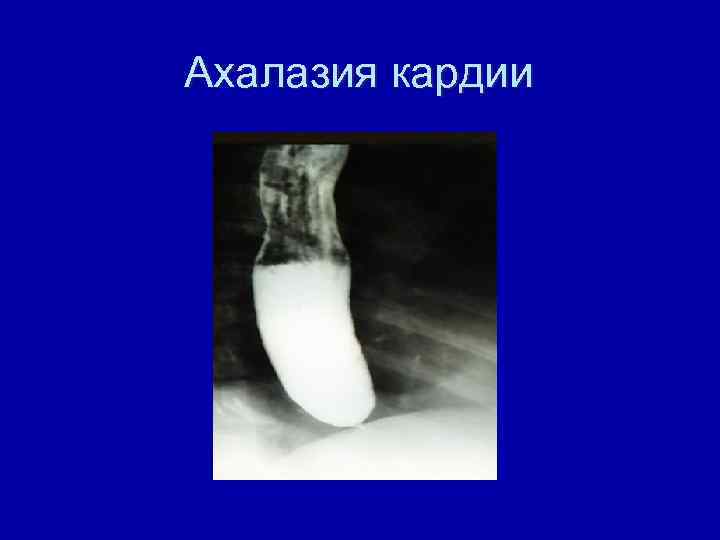

Ахалазия кардии